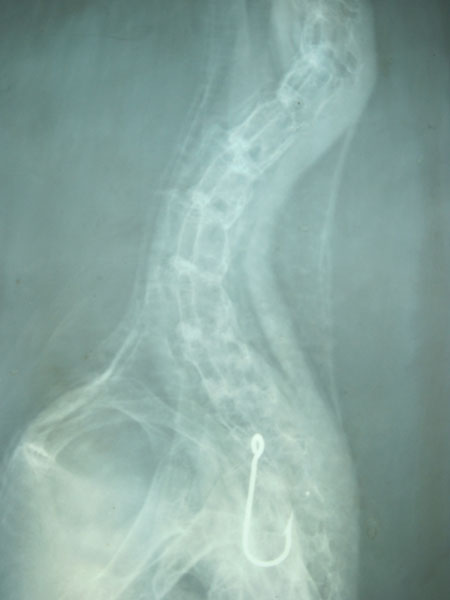

Raio-x de um ganso-patola com um anzol no tracto digestivo